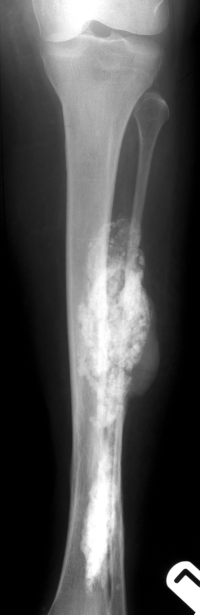

Osteofibrous dysplasia tibia. Typical anterior diaphyseal location, mixed lesion with minor anterior bowing. In an adult the differential diagnosis would include an adamantinoma.

10-year-old girl with mild pain and deformity of the shin.